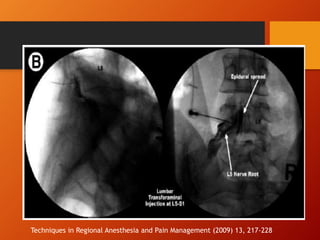

Techniques in Regional Anesthesia and Pain Management (2009) 13, 217-228

DESCRIPCION DE LA TECNICA

• Transforaminal Lumbar:

Bajo Guía fluoroscópica

Referencia anatómica

Triangulo de seguridad

Techniques in Regional Anesthesia and Pain

Management (2009) 13, 217-228

VIA TRANSFORAMINAL

TRIANGULO DE

SEGURIDADLIMITES:

Proceso transverso de la

vertebra superior.

Limite lateral: Borde del

foramen intervertebral:

Limite medial: Borde superior

del nervio

• Ubicación de la aguja en el

espacio epidural anterior

• (técnica convencional)

• Alternativa: ubicación de la

aguja en el espacio epidural

posterolateral.

• Aguja de punta roma,

número 22 y 24.

• Complicación por ubicación

intratecal menos frecuente.